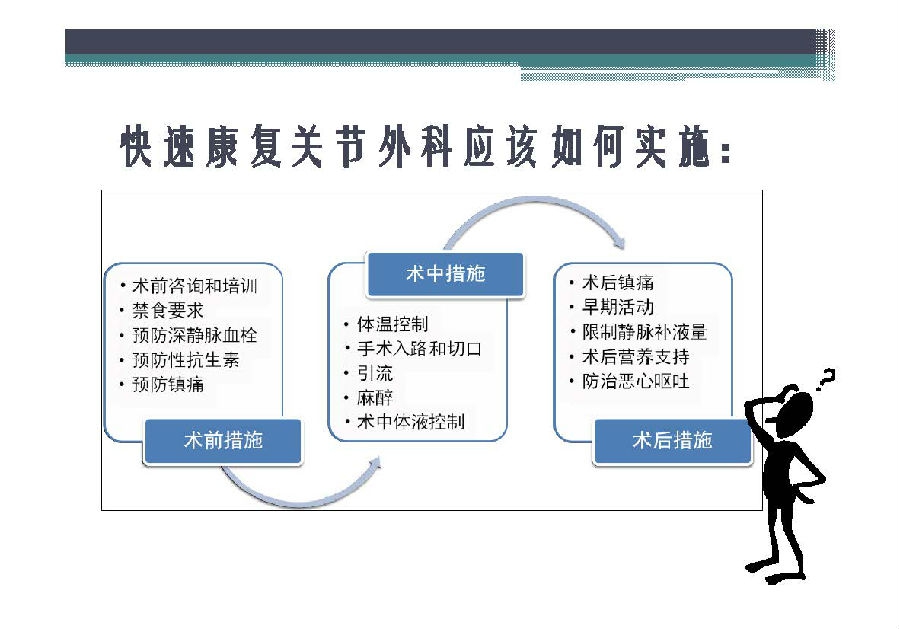

对于关节外科而言快速康复实际上是以病人加速舒适康复为目的,加强围术期的综合管理,包括疼痛和睡眠管理、血栓预防管理、感染预防管理、围术期血液管理,减少放置引流管、尿管、减少止血带应用,减少术后恶心呕吐,尽早进食,尽早康复等,逐步达到无血、无痛、无栓、无感、无肿、无管、无吐、无带等优良效果。为此,小编特邀王坤正教授等多位关节外科的专家参与撰写快速康复外科在关节外科的应用的主题文章,共话“人工关节置换快速康复”新理念,探讨建立符合我国特色的关节置换围手术期管理与快速康复体系,促进我国关节外科技术整体发展与提高。